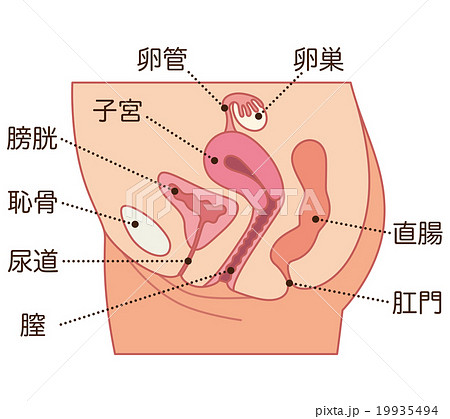

女性器の断面図 Listen さくやの囁き

子宮横からの断面図 名称付き メディカルイラスト図鑑 無料の医療 美容素材集

子宮 断面図 女性のからだのイラスト素材

骨盤 女性 解剖学 切断断面 卵巣 卵管 子宮 膀胱 膀胱 尿路 クリトリス 尿道 尿道括約筋 膣 外陰結腸 直腸括約筋が示される のイラスト素材

39 Best 子宮口 Images Stock Photos Vectors Adobe Stock